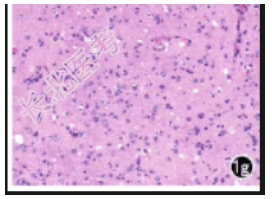

实验室检查:肌酸激酶同工酶GMB20U/L。影像学表现:MRI平扫左侧颞叶G海马区见不规则囊实性异常信号,边界欠清晰,大小约4.0cm×3.1cm,实性部分T1WI呈等、低混杂信号,T2WI、FLAIR呈高信号,DWI呈等、稍高信号;囊性部分大小约1.3cm×1.1cm,位于海马尾,信号欠均匀,T1WI、FLAIR、DWI呈中心低信号、边缘高信号,T2WI呈中心高信号、边缘低信号(图1a~1d)。增强扫描绕囊性病变周围斑片状轻度强化,其余未见强化(图1e、1f)。初步诊断为左侧颞叶G海马区低级别神经元胶质瘤。镜下示肿瘤细胞由大的神经节细胞及明显多样性的胶质细胞组成(图1g)。初步诊断为左侧颞叶节细胞胶质瘤。

说明:1a:T1WI轴面示病变实性部分呈等、低混杂信号,囊性部分呈中心低信号、边缘高信号;1b:T2WI示病变实性部分呈高信号,囊性部分呈中心高信号、边缘低信号(箭);1c:FLAIR示病变实性部分呈高信号,囊性部分呈中心低信号、边缘高信号;1d:DWI示病变囊性部分呈中心低信号、边缘高信号,实性部分呈等、稍高信号;1e:MRI增强扫描轴面示绕囊性病变周围斑片状强化(箭),其余未见强化;1f:MRI增强扫描冠状面示绕囊性病变周围斑片状强化(箭),其余未见强化;1g:镜下示肿瘤细胞由大的神经节细胞及明显多样性的胶质细胞组成(×200,HE)。